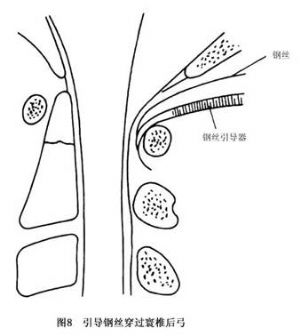

14.3.3 Gallie手术

Gallie手术多用于寰枢关节脱位明显者,如图8~10所示。先切取植骨块将其修成相应大小及所需的形状,之后将钢丝穿过寰椎后弓,再穿过枢椎两侧后弓下方收紧钢丝,使骨块嵌于颈1、2棘突之间即达复位及融合目的。本法的骨融合成功率较前者低,但对转颈活动影响较少。